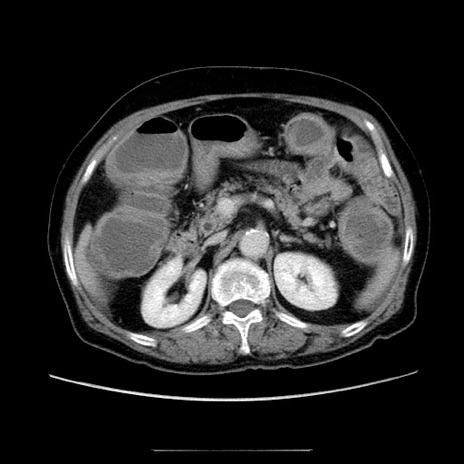

症例5(横断像)

【症例】70歳代女性

【主訴】お腹が張る

【現病歴】1週間くらい前から腹部膨満の自覚あり。昨日夜から増悪したため、本日救急外来受診。

【身体所見】意識清明、BT 36.5℃、BP 165/106mmHg、HR 80bpm、SpO2 98%、腹部:膨満、軟、自発痛・圧痛なし、触診にて不快感あり、腸蠕動音:減弱

【データ】WBC 12600、CRP 1.04